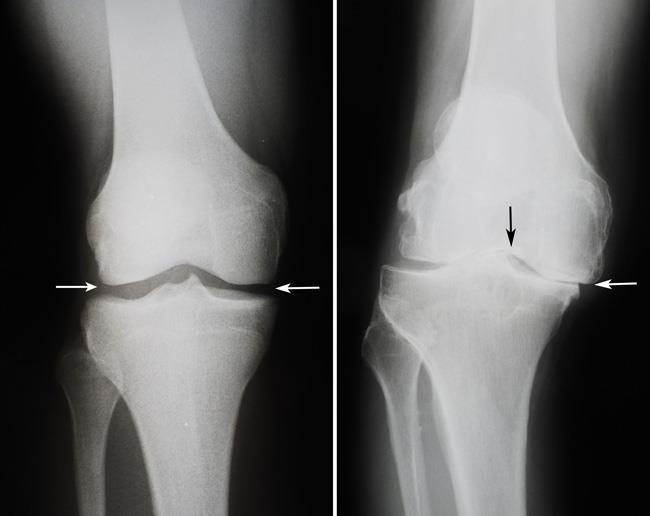

3. برای اطمینان بیشتر ، تصویر برداری با اشعه ایکس تجویز می کند تا میزان آسیب کلی به زانو مشخص شود .

عکس برداری از مفصل سالم (سمت چپ) و تفاوت آن با مفصل آسیب دیده (سمت راست) عکس برداری از مفصل سالم (سمت چپ) و تفاوت آن با مفصل آسیب دیده (سمت راست)